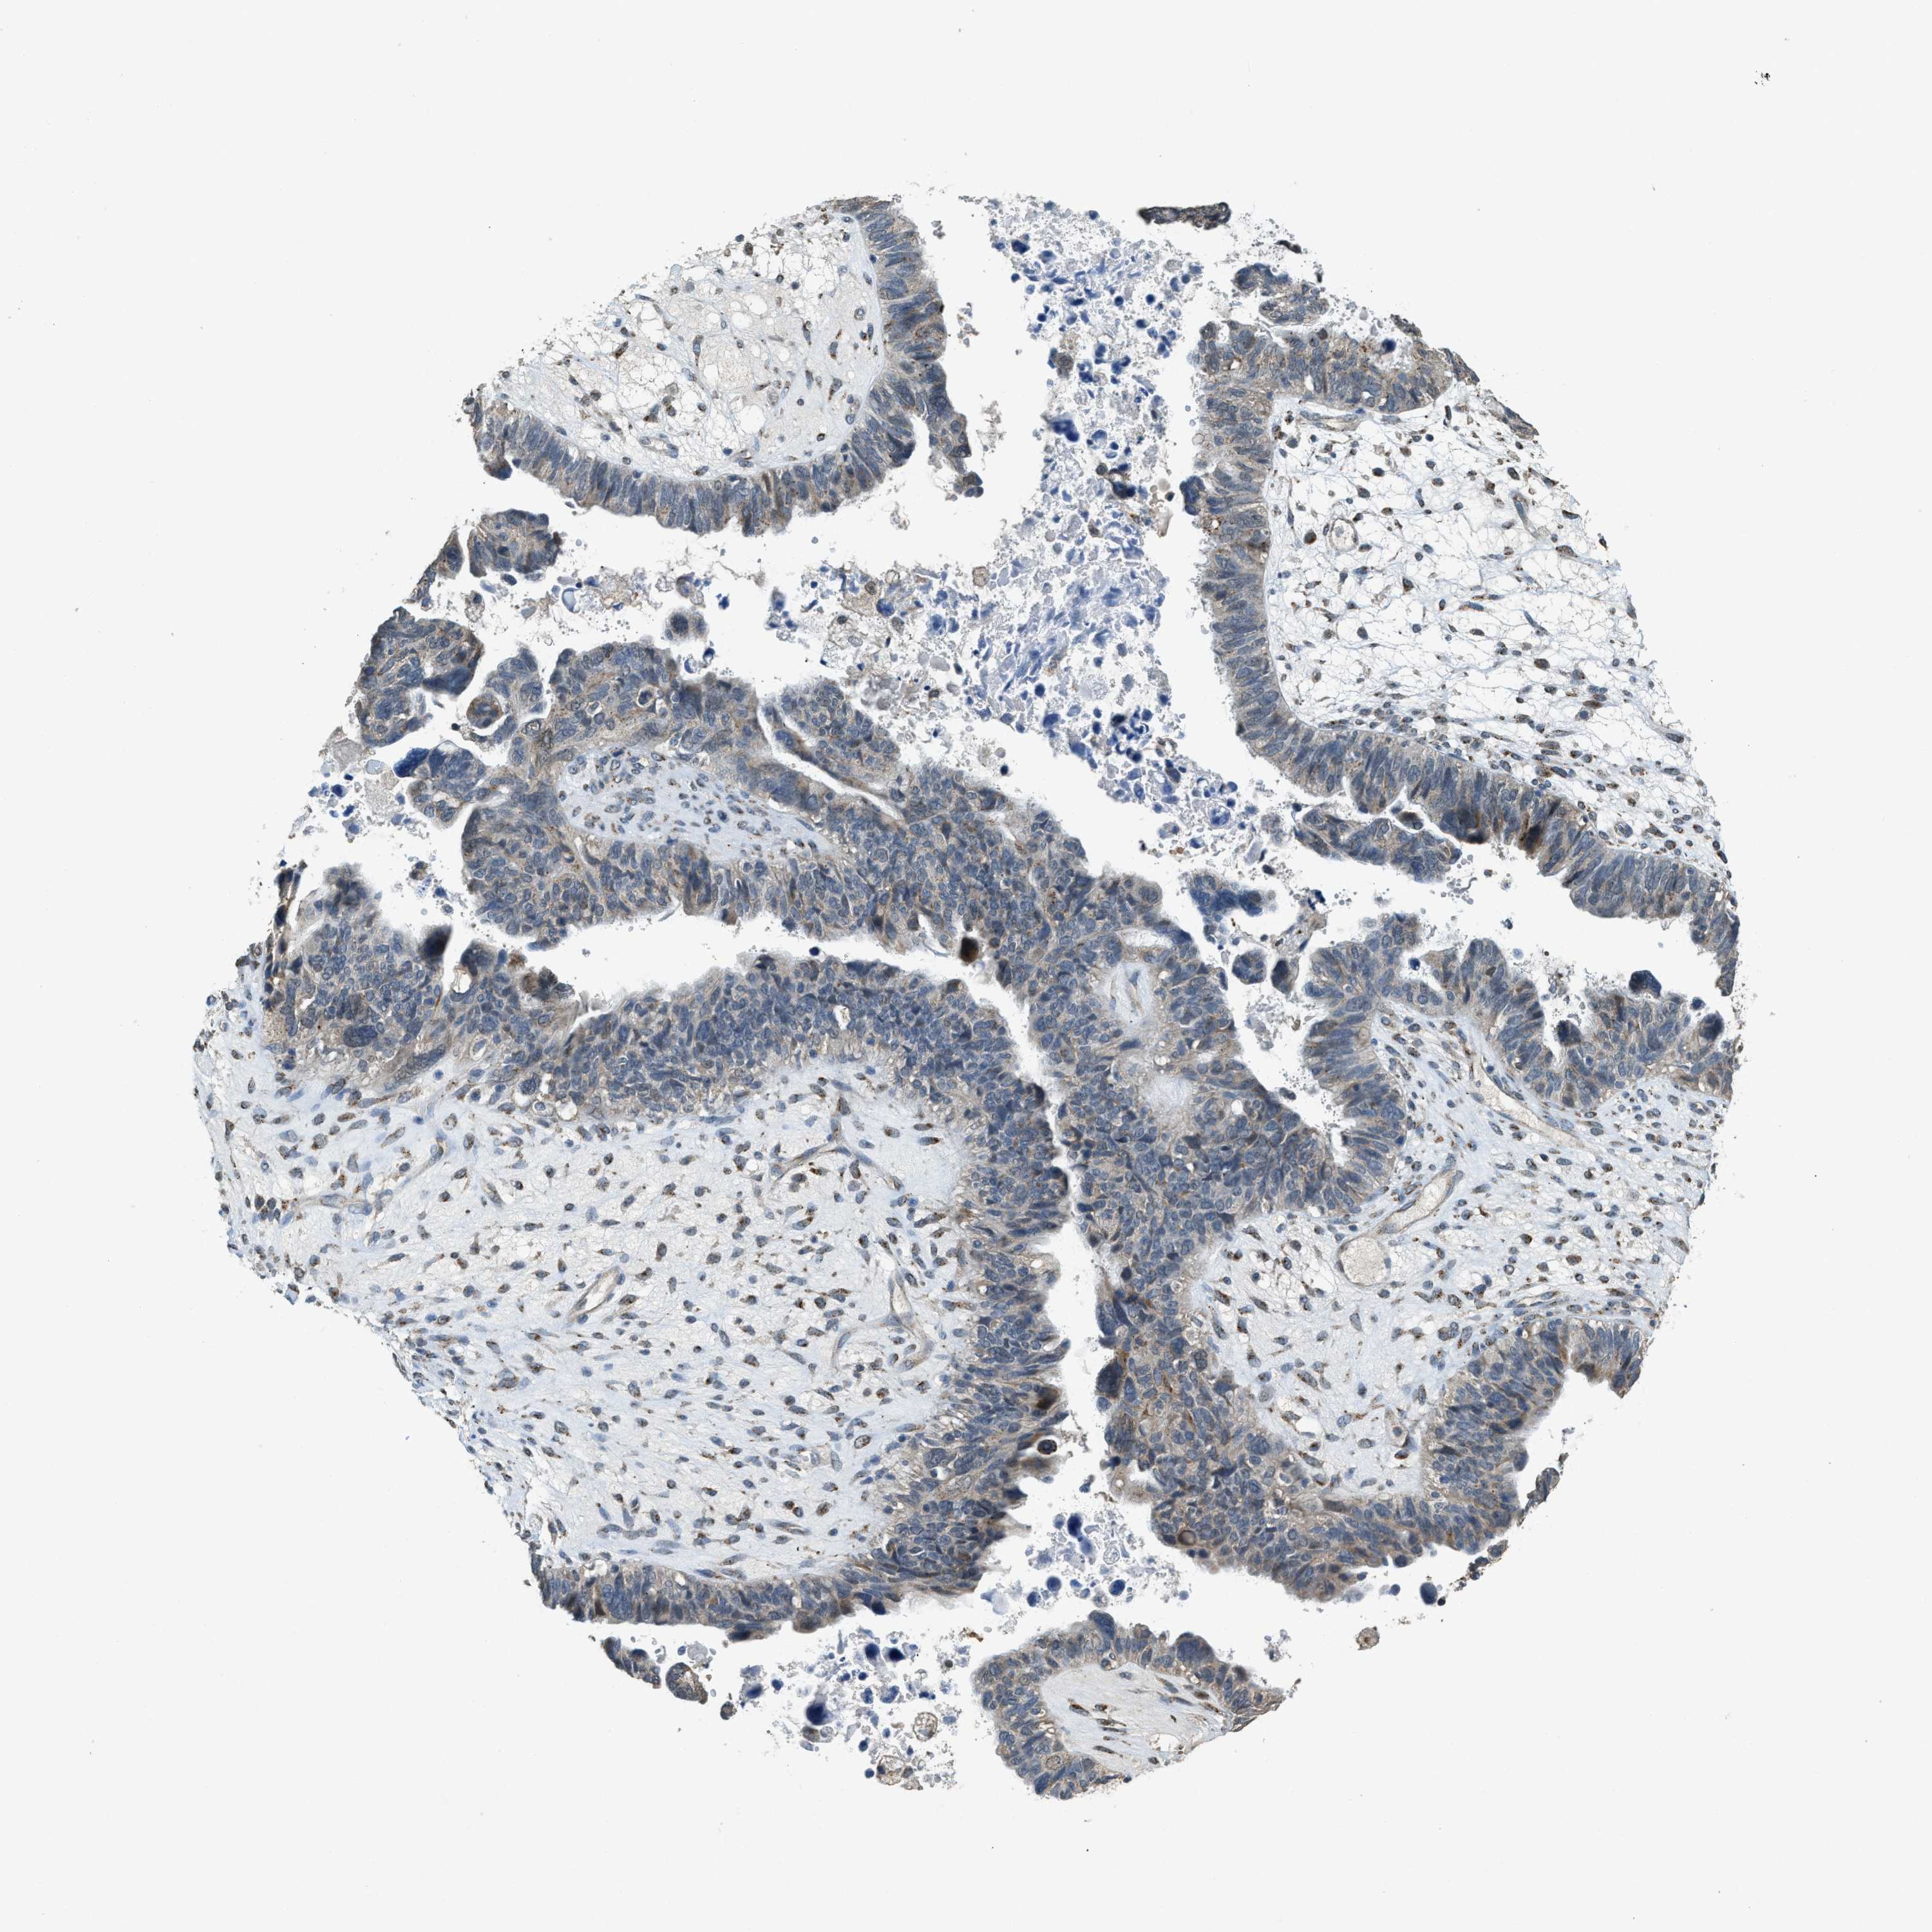

OVARIAN CANCER - Protein expressioni

A mouse-over function shows sample information and annotation data. Click on an image to view it in a full screen mode. Samples can be filtered based on level of antibody staining by selecting one or several of the following categories: high, medium, low and not detected. The assay and annotation is described here.

Note that samples used for immunohistochemistry by the Human Protein Atlas do not correspond to samples in the TCGA dataset.

Antibody stainingi

Antibody staining in the annotated cell types in the current human tissue is reported as not detected, low, medium, or high, based on conventional immunohistochemistry profiling in selected tissues. This score is based on the combination of the staining intensity and fraction of stained cells.

Each image is clickable and will lead to virtual microscopy that enables deeper exploration of all samples and also displays staining intensity scores, fraction scores and subcellular localization as well as patient and tissue information for each sample.

Antibody HPA019002

Staining

High

Medium

Low

Not detected

Intensity

Strong

Moderate

Weak

Negative

Quantity

>75%

75%-25%

<25%

None

Location

Nuclear

Cytoplasmic/membranous

Cytoplasmic/membranous,nuclear

Cystadenocarcinoma, serous, NOS

Carcinoma, endometroid

Cystadenocarcinoma, mucinous, NOS

Carcinoma, NOS